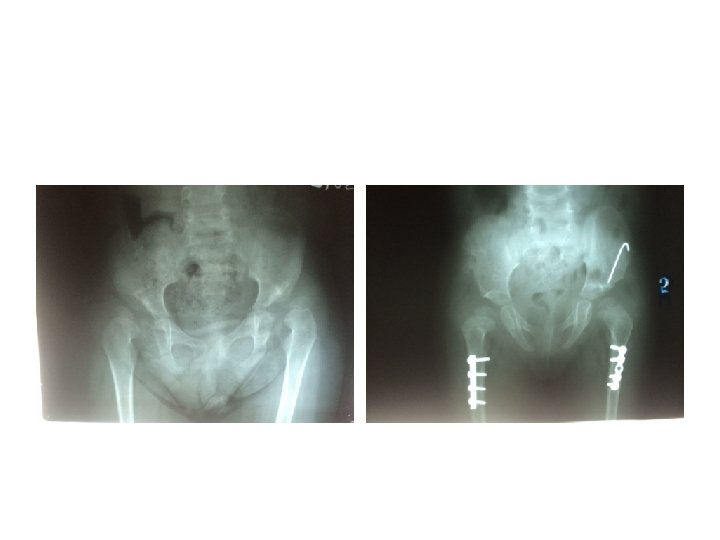

Somerville technique of anterior open reduction in congenital dislocation of hip. A, Bikini incision.

Somerville technique of anterior open reduction in congenital dislocation of hip. A, Bikini incision. B, Division of sartorius and rectus femoris tendons and iliac epiphysis. C, T-shaped incision of capsule. D, Capsulotomy of hip and use of ligamentum teres to find true acetabulum. E, Radial incisions in acetabular labrum and removal of all pulvinar from depth of true acetabulum. F, Reduction and capsulorrhaphy after excision of redundant capsule. G, Developmental dislocation of right hip. H, After anterolateral open reduction. I, At age 7 years; note remodeling of femoral head and acetabulum.